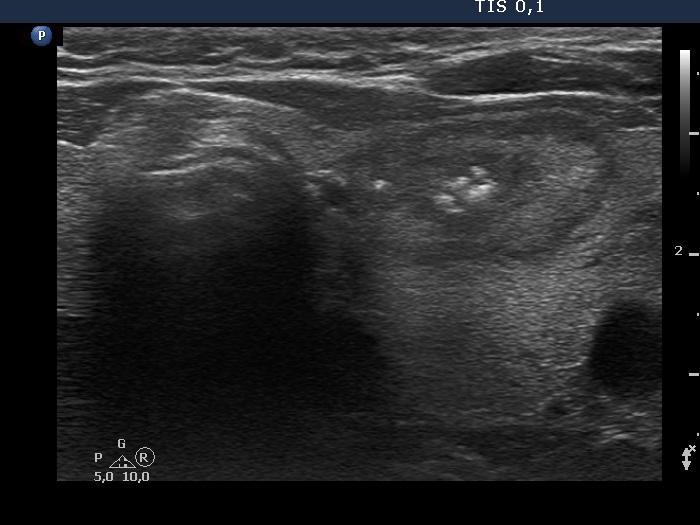

Ultrasonography. The thyroid was echonormal and contained several nodules of different echogenicities including a hypoechogenic one in the dorsal part of the left lobe and a minimally hypoechogenic lesion presenting groups of echogenic foci in the ventral part of the left lobe.

The origin of the echogenic foci within the left nodule is equivocal. They probably correspond to groups of smaller echogenic foci.